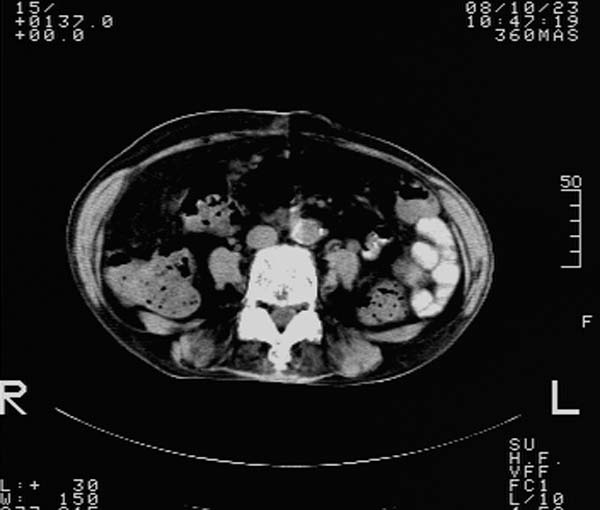

f,67y。反复右上腹痛。余无异常。

前五幅未服造影剂。后面图像有上传重复的。请战友们发表意见。

胆囊结石、胆囊癌伴邻近脏器受侵,不除外黄色肉芽肿性胆囊炎,建议增强扫描。肝多发囊性占位性病变,囊肿或囊性转移。

胆囊内结石,胆囊壁不规则增厚,胆囊胃窦区解剖结构欠清晰,楼主提示为少见病,考虑bouveret综合征?黄色肉芽肿性胆囊炎?肝内多发低密度占位,建议增强或b超

bouveret综合征(胆石性十二指肠幽门梗阻)应重点考虑。期待结果!

考虑bouveret综合征?黄色肉芽肿性胆囊炎?肝内多发低密度占位,囊肿?建议增强!